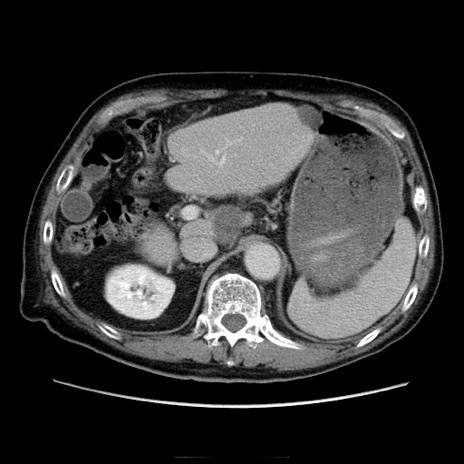

冠状断像

【症例】70歳代男性

【主訴】腹痛

【現病歴】肝硬変・肝細胞癌にてかかりつけの方。約9時間前に食後より腹痛出現。症状が徐々に増悪し、嘔吐出現したため来院。

【既往歴】肝硬変、肝細胞癌(RFA、TACE後)

【身体所見】意識清明、表情苦悶様、BT 36℃、BP 129/78mmHg、P 88bpm、SpO2 97%(RA)、右上腹部から心窩部にかけて圧痛あり、反跳痛なし、筋性防御あり。

【データ】WBC 5800、CRP 0.16